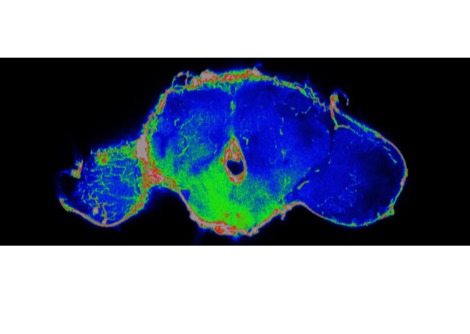

زاد النظام الغذائي عالي الدهون من الخلايا التائية الملتهبة وخفض عدد الخلايا التائية التنظيمية الملتهبة ( Tregs ) في الشريان الأبهر وهو أكبر وعاء دموي في الجسم والذي قام الباحثون بدراسته كمثال على ما كان يحدث داخل الأوعية الدموية عند الجنسين.

ظهرت هنا بعض الفروق بين الجنسين. تمتلك الإناث عادة نسبة أعلى من Tregs مما يساعدهن على خفض ضغط الدم، وفيما يعاني كلًأ من الذكور والإناث من الانخفاض في هذه النسبة تحافظ الإناث على النسبة الأعلى بغض النظر عما يستهلكنه. أظهرت دراسات أخرى أن الإناث تستجيب للعوامل التي يمكن أن تزيد من ضغط الدم مثل الملح أو الدهون عن طريق زيادة نسبة Tregs وتحافظ على ضغط جيد.